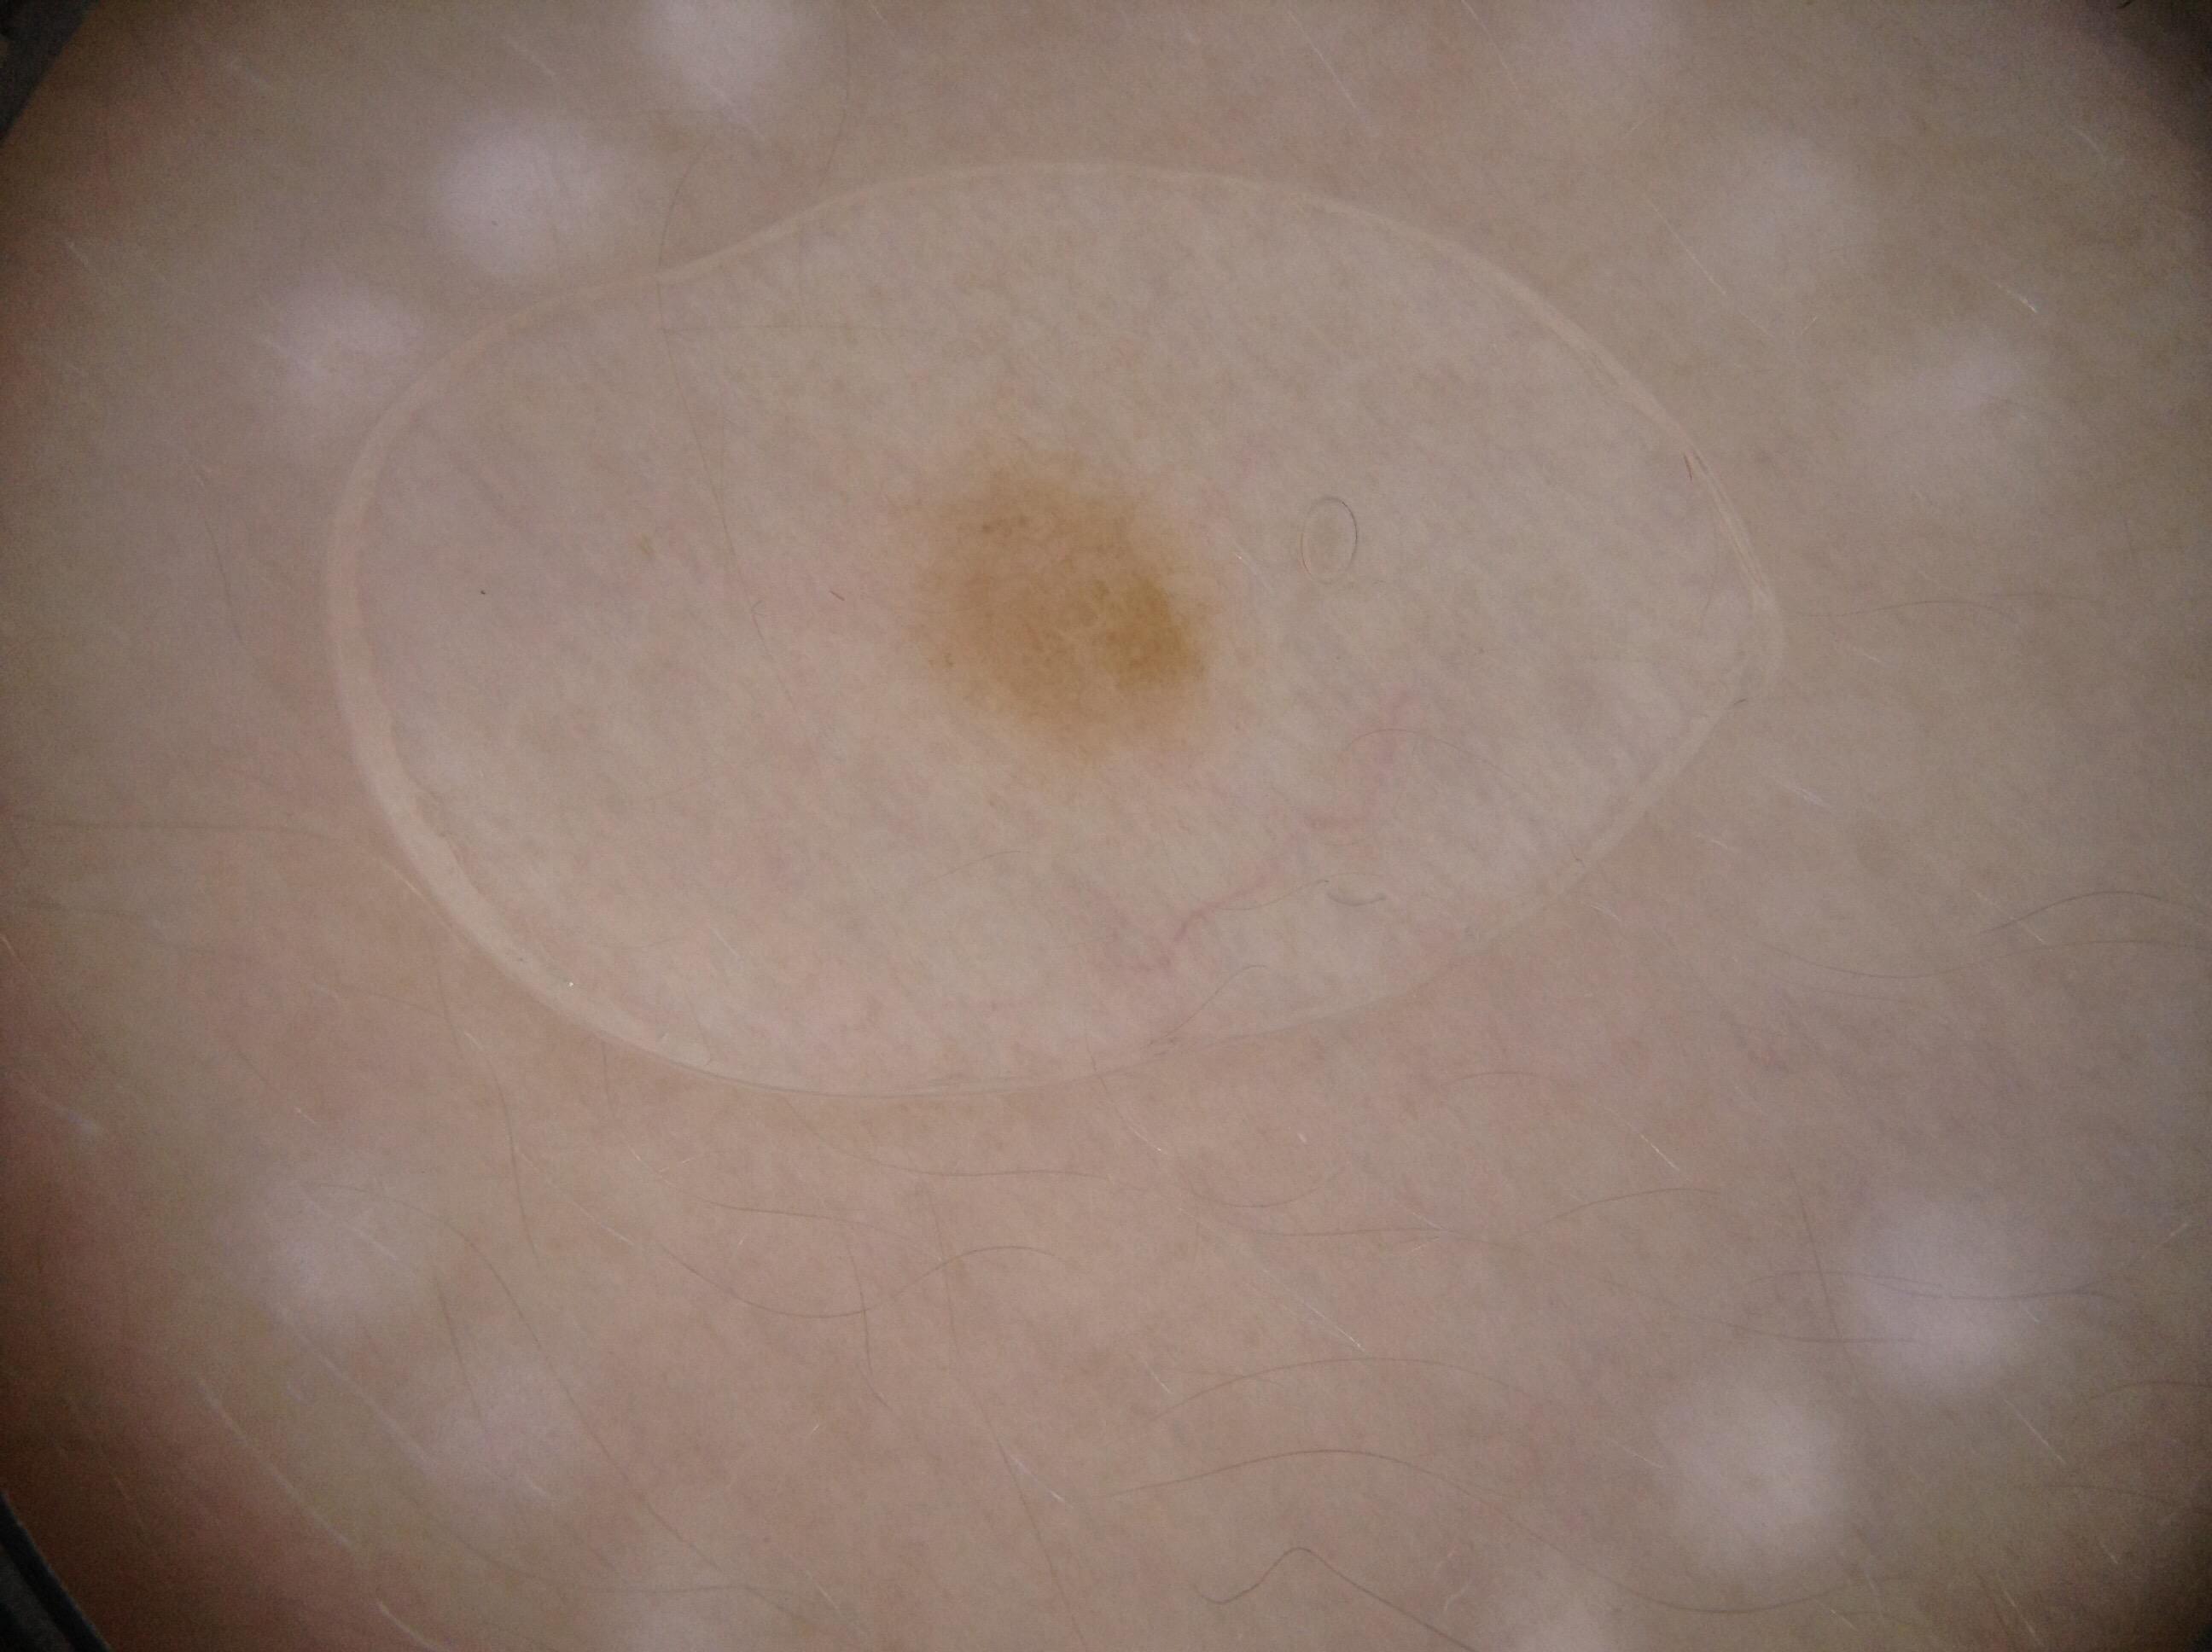

{

"acquisition_day": 1,

"age_approx": 45,

"anatom_site_general": "anterior torso",

"concomitant_biopsy": false,

"diagnosis_1": "Benign",

"diagnosis_confirm_type": "single image expert consensus",

"image_manipulation": "instrument only",

"image_type": "dermoscopic",

"lesion_id": "IL_7004367",

"patient_id": "IP_0775515",

"sex": "male"

}